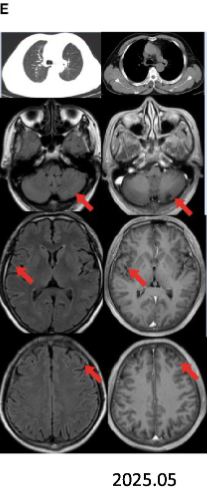

患者男性,60岁,有吸烟史,因“咳嗽、头痛1个月”于2023年10月入院。头痛视觉模拟评分(VAS)为6/10分,无其他神经系统症状。

左肺上叶腺癌(cT2bN1M1c1,ⅣB期)伴多发脑转移。

疗效评估

术后继续予伏美替尼辅助治疗,随访至2025年5月(术后18个月),头颅MRI示无复发灶,肺部及脑部均未发现肿瘤复发。